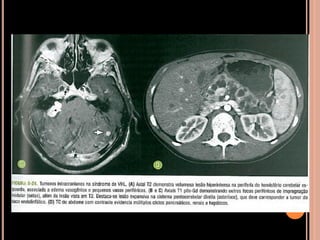

DOENÇA DE VON-HIPPEL LINDAU

 Hemangioblastomatose

 Tumores benignos e malignos múltiplos;

 Hemangioblastomas de retina, cerebelo e medula

espinhal;

 Rins: carcinoma de células renais;

 Adrenais: feocromocitoma;

 Pâncreas: tumores de células de ilhota e

adenomas serosos;

 Testículos: cistoadenomas epididimários;

 Cistos renais e pancreáticos múltiplos;

 1/3 dos hemangioblastomas cerebelares

relacionados à síndrome de VHL;

 2/3 dos hemangioblastomas medulares

 Associados à síndrome  idade mais precoce e

pior prognóstico;